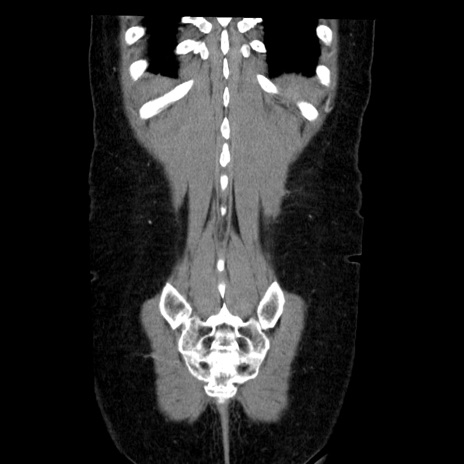

症例6(冠状断像)

【症例】50歳代女性

【主訴】下腹部痛

【既往歴】卵巣癌術後(8年前に当院で卵巣摘出)